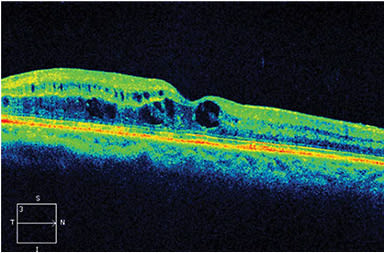

Given the patient’s poor response to anti-VEGF monotherapy, she was switched to a combination of Lucentis followed by the dexamethasone intravitreal implant (Ozurdex, Allergan) 2 weeks later. At the start of the combination therapy, the patient’s visual acuity was 20/100, and her CFT was 565 µm (Figure 1).

Figure 1. Prior to starting combination therapy, visual acuity was 20/100, and CFT was 565 µm.